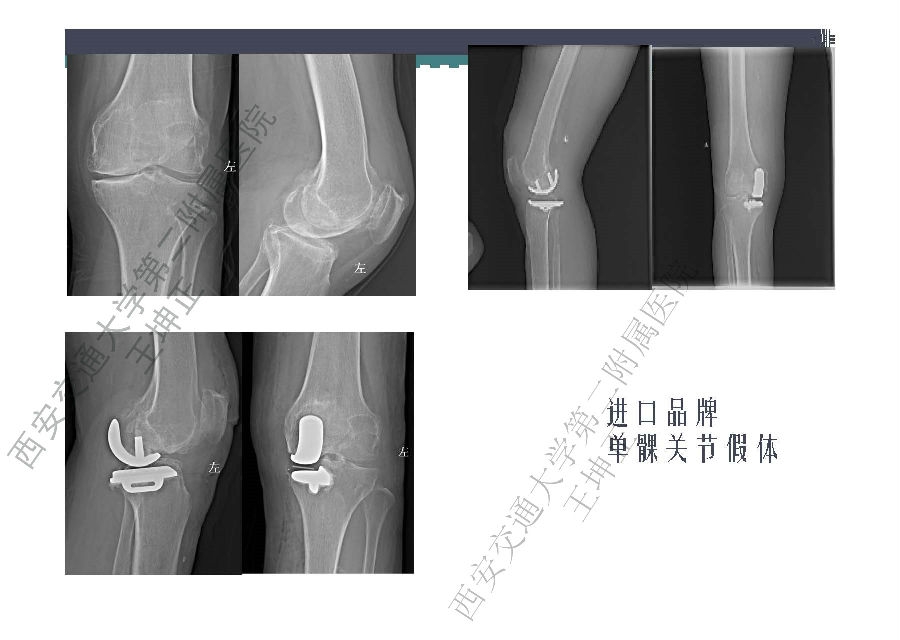

对于关节外科而言快速康复实际上是以病人加速舒适康复为目的,加强围术期的综合管理,包括疼痛和睡眠管理、血栓预防管理、感染预防管理、围术期血液管理,减少放置引流管、尿管、减少止血带应用,减少术后恶心呕吐,尽早进食,尽早康复等,逐步达到无血、无痛、无栓、无感、无肿、无管、无吐、无带等优良效果。为此,小编特邀王坤正教授等多位关节外科的专家参与撰写快速康复外科在关节外科的应用的主题文章,共话“人工关节置换快速康复”新理念,探讨建立符合我国特色的关节置换围手术期管理与快速康复体系,促进我国关节外科技术整体发展与提高。